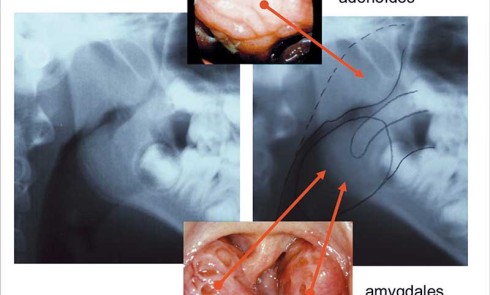

Article réservé à nos abonnés Ventilation buccale et SAOS chez l’enfant

Ventilation buccale La nécessité vitale de la permanence des échanges gazeux au niveau des alvéoles pulmonaires confère un rôle capital...